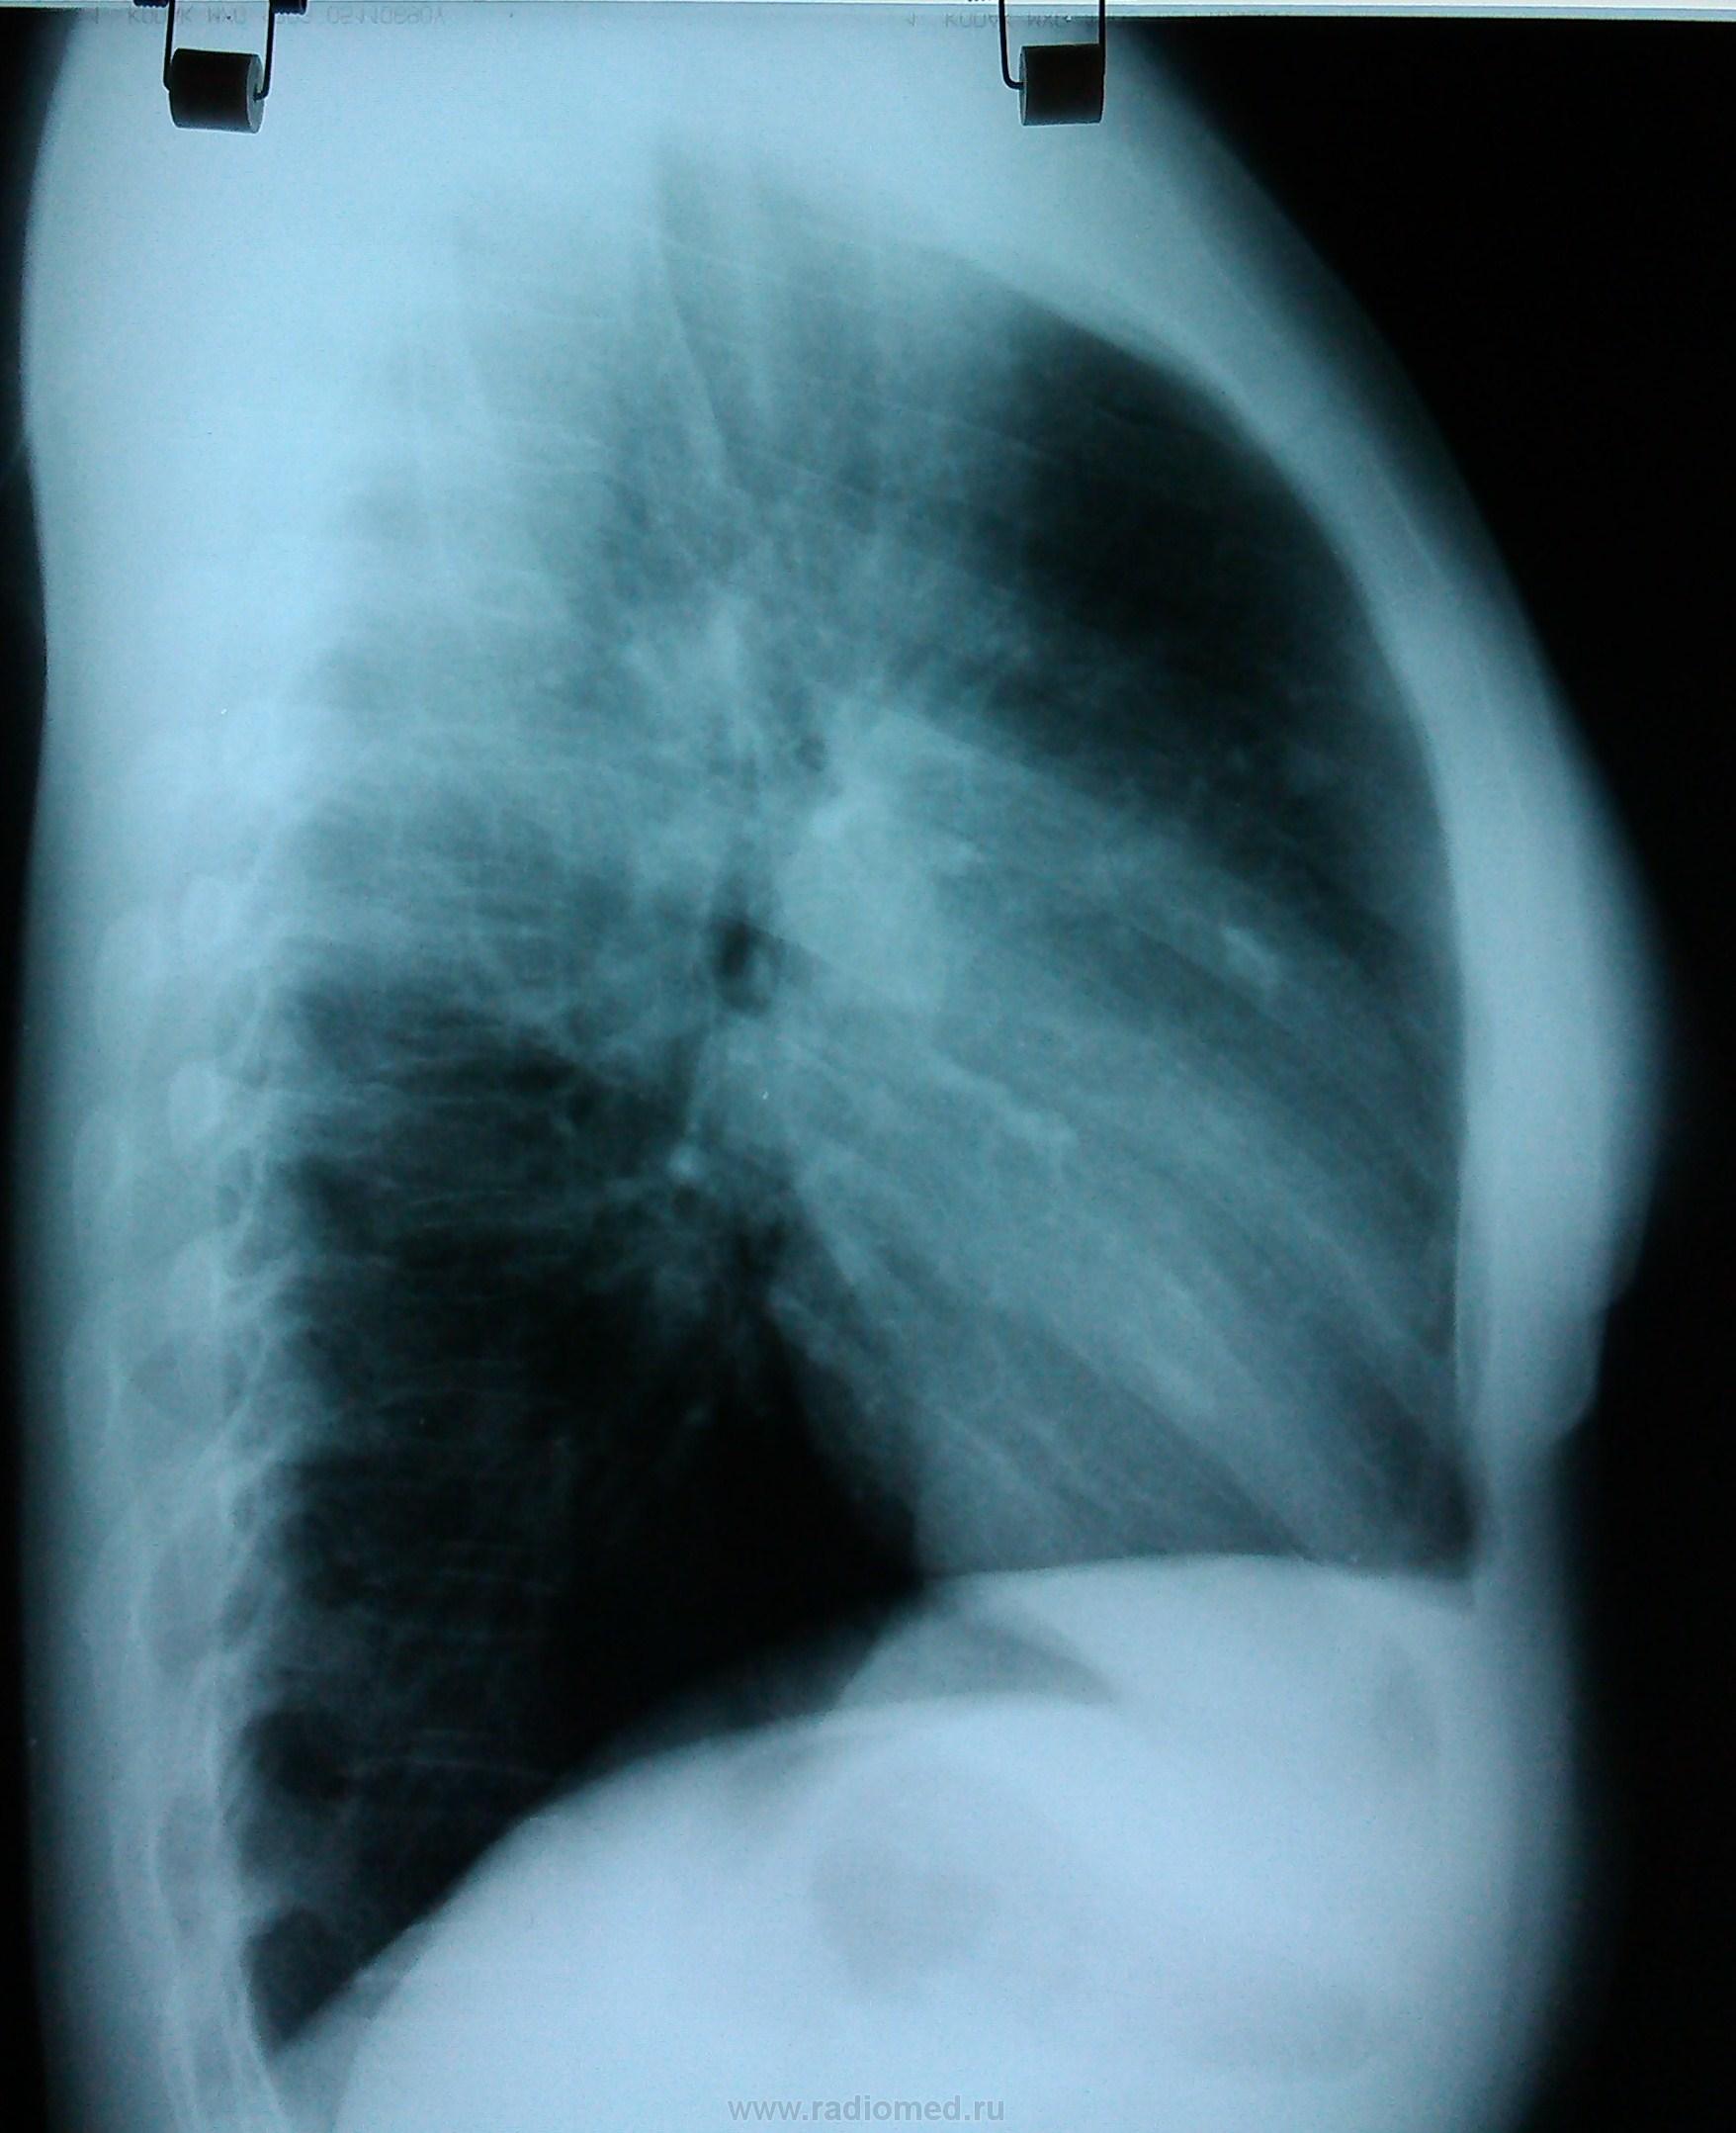

Сначала, в 11 году, был плотный очаг. К 2013 очевидно подрос, вполне может оказаться периферической опухолью.

легочный аффект в S3 правого легкого с очередной вспышкой. Показано обследование в ПТД.

Петирфикат справа в S3 ( возможно в Sax )-если есть сомнения, возмите пациентку на R-скопию лёгких-определитесь с топографией изменённого участка ( имеет отношение к лёгочной ткани? какой сегмент ? и др.)

Периферический растет...

На боковом интересные "очаговые" тени...

Очаговые тени в переднем сегменте. В дифряд - мальформация.

Прямая и боковая разнятся (на мой взгляд) за счет суммации изображений обоих легких на боковой рентгенограмме. При всем уважении к линейной ТГ - в конкретном случае (молодая женщина, визуальный рост "очага", относительно малые его размеры, три года наблюдения, доверие клиницистов к КТ) сразу постарался бы найти возможность для КТ.

Обработанные снимки.